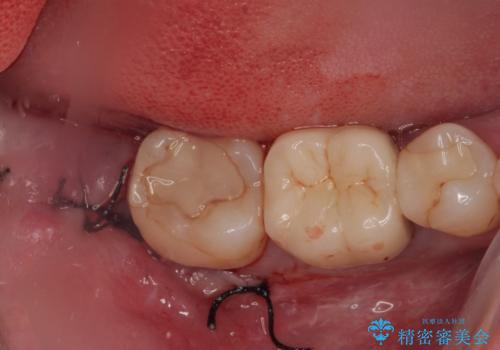

左下の奥歯が欠けた フルジルコニアクラウン・親知らず抜歯

担当医 有澤哲郎